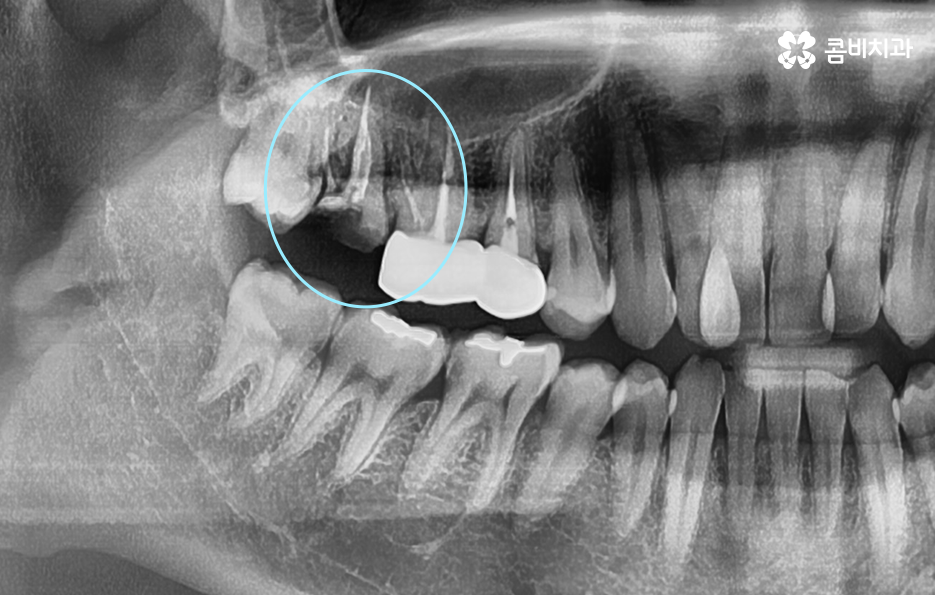

오늘은 자연치아를 결국 잃게 되면 대표적인 사례 중에서 오래된 보철물 혹은 보철물 관리가 잘 안되어 결국 발치로 이어지는 사례에 대해서 알아볼 거예요. 오래된 보철물 속에서 진행되는 2차 충치는 알아차리기도 쉽지 않고 이미 깊어지면 치아 뿌리 쪽으로 충치가 진행되어 발치로 이어지는 경우가 많다는 점에서 보철물 관리의 중요성에 대해서 재인식하는 포스팅이 되길 바라고 있어요

보통 어금니 크라운을 씌운 경우에는 신경치료를 한 후에 크라운을 씌운 경우가 많기 때문에 이미 크라운 속에 충치가 심하게 진행되어도 통증과 같은 증상으로 문제를 잘 못느끼는 경우가 많이 있는데요

치아 문제에 대해서 안아프면 별 문제 없겠지 하고 잘 지내고 있다가 예전에 씌워서 기억도 잘 안나는 크라운이 흔들리거나 냄새, 잇몸 염증 등이 발생하여 치과를 찾게 되었는데 이미 심각한 수준으로 치아 내부에 충치가 진행되어 결국 발치에 이르게 되는 경우가 많이 있어요

크라운 혹은 오래된 보철물 내부에 2차 충치가 발생된 경우에 자연치아를 보존할 수 있는지에 대한 판단은 엑스레이 만으로 진단할 수 있는 문제는 아니며 치아 내부에 충치가 어느정도나 진행되었고 잔존하는 치아의 양이 어느정도나 되는지에 따라서 발치 혹은 치아 보존 치료에 대한 판단을 할 수 있어요

이미 신경치료를 했던 치아라고 해도 보철물 제거 후에 충치를 잘 치료하고 재신경치료를 통해서 치아를 보존할 수 있는 경우가 있고 발치 후 임플란트를 해야하는 경우도 있는데요

이러한 판단 기준은 치아 내부에서 충치가 발생되었을 때 충치가 얼마나 치아 뿌리 쪽으로 깊어졌는지 혹은 살릴 수 있는 치아가 얼마나 잔존하는지에 따라서 다르며 치과의사 역시도 치아 속을 확인해보고 충치를 제거해봐야 알기 때문에 치과의사의 숙련도, 경험도 중요하겠지만 치과의 내원 시점이 무척이나 중요하기 때문에 보철물이 오래된 경우에는 꼭 주기적으로 치과 검진을 하시고 의사의 소견 하에 크라운의 교체가 필요하다면 문제가 커지기 전에 재치료를 적절히 받는 것이 자연치아 보존에 중요할 거예요